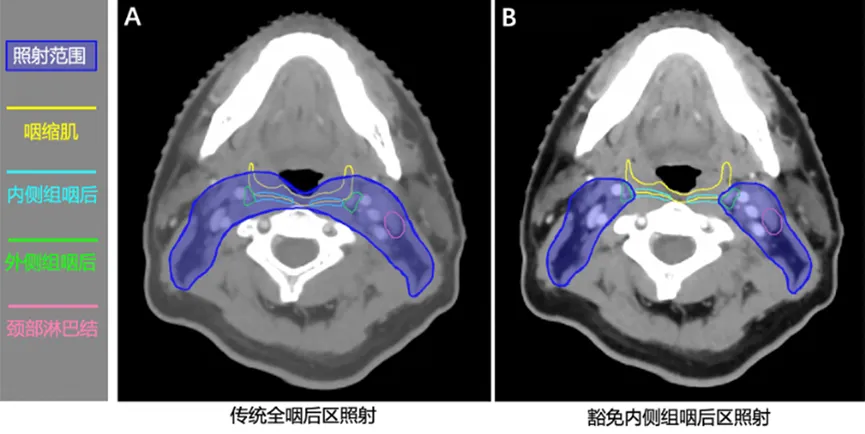

该项研究是一项开放标签、非劣效、多中心、随机对照的3期临床试验(NCT03346109)。主要入组标准包括年龄在18-65岁的初治、非角化型鼻咽癌患者(T1-4N0-3M0),且KPS评分>70;其中存在影像学可疑或明确的内侧组咽后淋巴结受累的患者被排除。符合条件的患者1:1随机分配至内侧组咽后淋巴结区豁免放疗组或标准放疗组(图1)。主要研究终点为无局部复发生存率。本次报告更新了5年随访的疗效、安全性和生活质量结果。此外,本次报告还增加了基于造影检查的吞咽功能客观评估以及基于磁共振的咽缩肌厚度测量。

图1:内侧组咽后区豁免放疗新技术